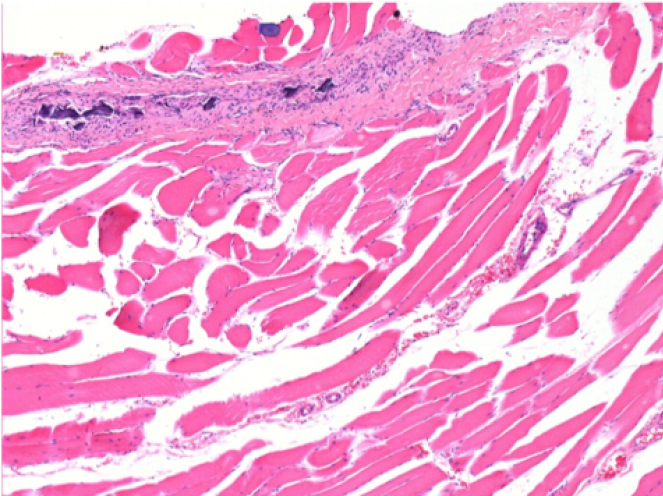

7 months (D210)after Endopeel IM Injection 0.1ml in the right pretibial muscle.

Complete Restitutio ad integrum after 7 months

L :Control 50xD210

R50X-D210